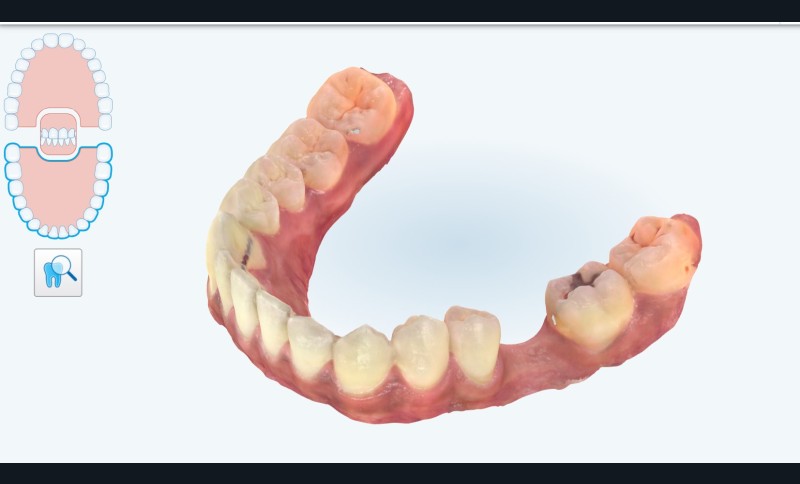

Pour cela nous décidons de poser notre implant de façon « Full guidé », c’est-à-dire planifié en amont dans une position alliant un placement optimal osseux et prothétique. Nous aurons besoin d’une empreinte numérique qui va nous fournir un fichier STL (fig. 1) , ainsi que les information sur l’os fournies par le cone-beam (CBCT) . Nous décidons à ce stade de faire modéliser le guide par une plateforme de conception (design4me) qui s’occupera du matching de nos DATA. Après validation de la planification nous recevons notre fichier (fig. 2) prêt à être imprimé localement grâce à une imprimante 3D (Nextdent).